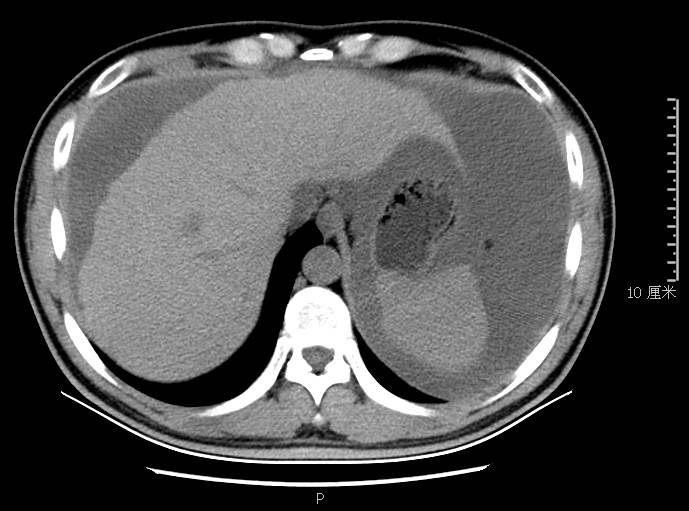

全腹CT:(1)结合病史考虑腹膜炎(见图2A),大量腹水;(2)右骼窝区管状样结构,考虑阑尾扩张(见图2B);(3)肝脏多发小囊肿(见图2C);(4)肝内胆管轻度扩张,建议隔期复查。

本例确诊后对B超及CT再次回忆发现:腹腔、盆腔可见不均质中强回声包块,部分呈囊实状,腹膜增厚,大网膜成饼状(如图2A)和肝周可见不均质中强回声弧形压迹、脾周可见不均质中强回声包饶,肝脏成扇贝样改变(如图2C),但在诊断报告中未提及。有学者发现mantle和scalloping(如图2A,2C)在PMP中具有代表性,且mantle较scalloping更为常见,若mantel征同时伴有大小不一的囊性改变,则更具诊断价值。

图2c肝脏成扇贝样改变(肝脏由于受肿瘤实质性或囊性策划压迫而其实质却未受侵犯,于是在一处或多处呈下凹状或扇形皱褶状(scalloping)

通过本病例分析认为此类患者,腹穿时若发现腹水不易抽出或抽出物为黏稠胶冻样,腹部B超提示液性暗区内有漂浮的团状回声有分隔,撞击腹部后可出现“礼花”样改变,肝脾包膜完整不光滑,有弧形压迹,全腹部CT示弥散占位,可见mantle和scallping征、大网膜成饼状且阑尾扩张应高度怀疑本病。